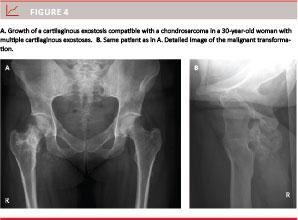

Malignant transformation is extremely rare in the paediatric patient [1-16], but seems to occur around the age of 30 years with an increasing risk with age (Figure 4) [1, 2, 3, 12].

Malignant transformation causes a surface irregularity and unorganised chalk deposits with light areas in the middle of the tumour as well as in the cartilage cap. Sometimes calcifications are seen in the surrounding organs [2, 9]. However, definitive diagnosis requires a biopsy.